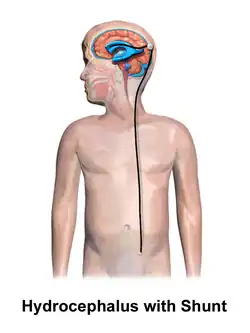

Hydrocephalus is treated through surgery by creating a way for the excess fluid to drain away. An external ventricular drain (EVD), also known as an extraventricular drain or ventriculostomy, provides relief in the short term.[48] In the long term, some people will need any of the various types of cerebral shunts.[48] It involves the placement of a ventricular catheter (a tube made of silastic) into the cerebral ventricles. This creates a way to bypass the flow obstruction/malfunctioning arachnoidal granulations. The excess fluid drains into other body cavities where it can be resorbed. Most shunts drain the fluid into the peritoneal cavity (ventriculoperitoneal shunt).[49] Other shunts drain the fluid into the right atrium (ventriculoatrial shunt), pleural cavity (ventriculopleural shunt), and gallbladder.[49]

A shunt system can also be placed in the lumbar space of the spine. This allows the excess fluid to be redirected to the peritoneal cavity (lumbar-peritoneal shunt).[50] Another treatment for obstructive hydrocephalus is an endoscopic third ventriculostomy (ETV). This surgery creates an opening in the floor of the third ventricle so that CSF flows directly to the basal cisterns. This treatment can shortcut any obstruction like aqueductal stenosis. This may or may not be appropriate based on individual anatomy. Some infants can be treated with ETV and choroid plexus cauterization.[51][52] Choroid plexus cauterization reduces the amount of cerebrospinal fluid produced by the brain. The technique, known as ETV/CPC, was pioneered in Uganda by neurosurgeon Benjamin Warf and is now in use in several U.S. hospitals.[51][52]